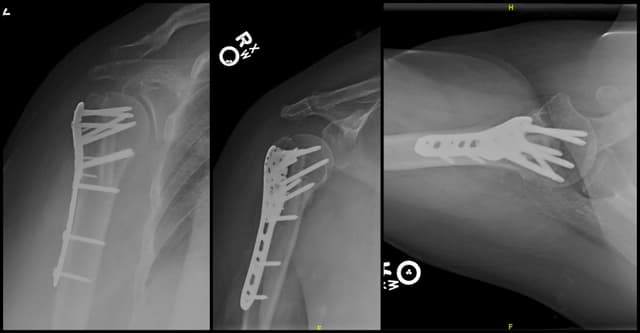

Imaging

Post-op